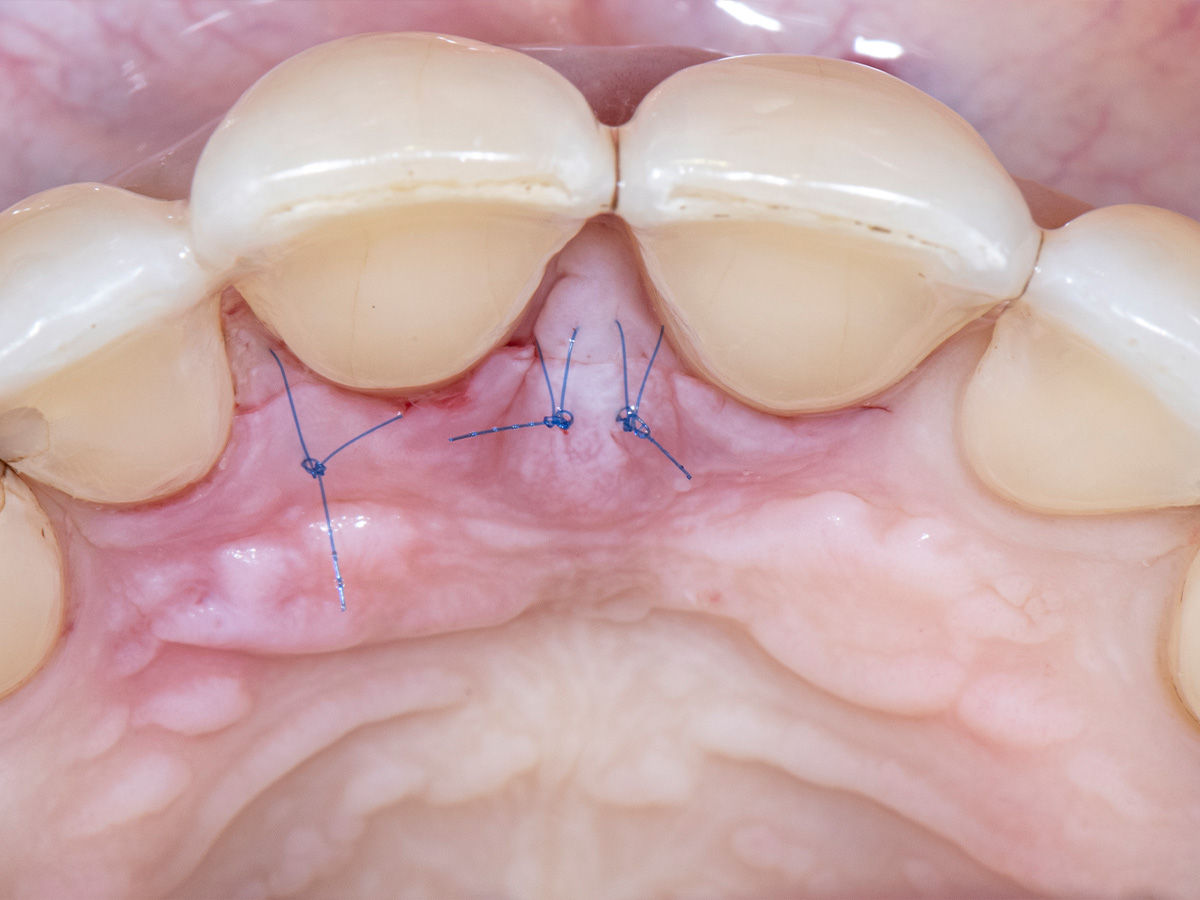

Nach gründlicher Reinigung...

wurden autogene Knochenspäne sowie Schmelzmatrixproteine appliziert...

und die Lappenenden mit Nähten spannungsfrei adaptiert, um eine Heilung per primam zu ermöglichen.